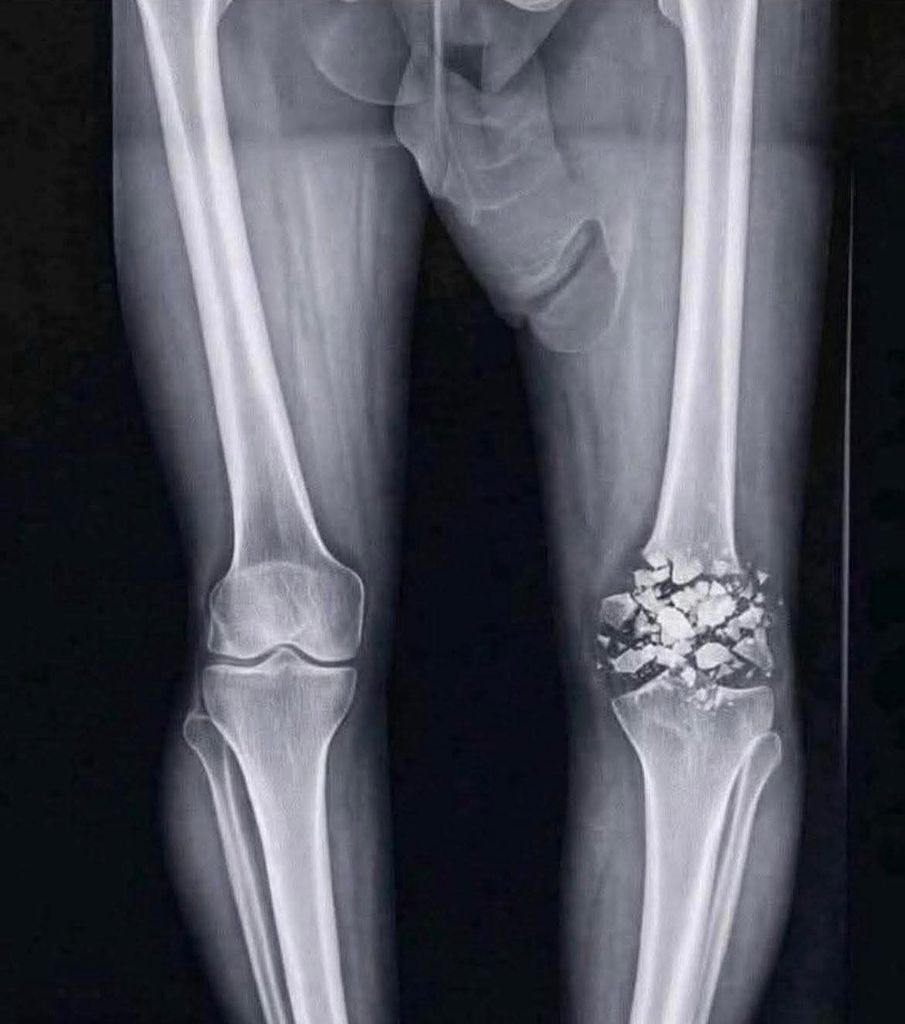

Grosse grosse douleur au genou suite a une chute ce matin .

La radio a confirmé mes peurs , regardez l'etat du genou:

Attention image sensible

AYAAAA rotule en miettes mon pauvre je compatis